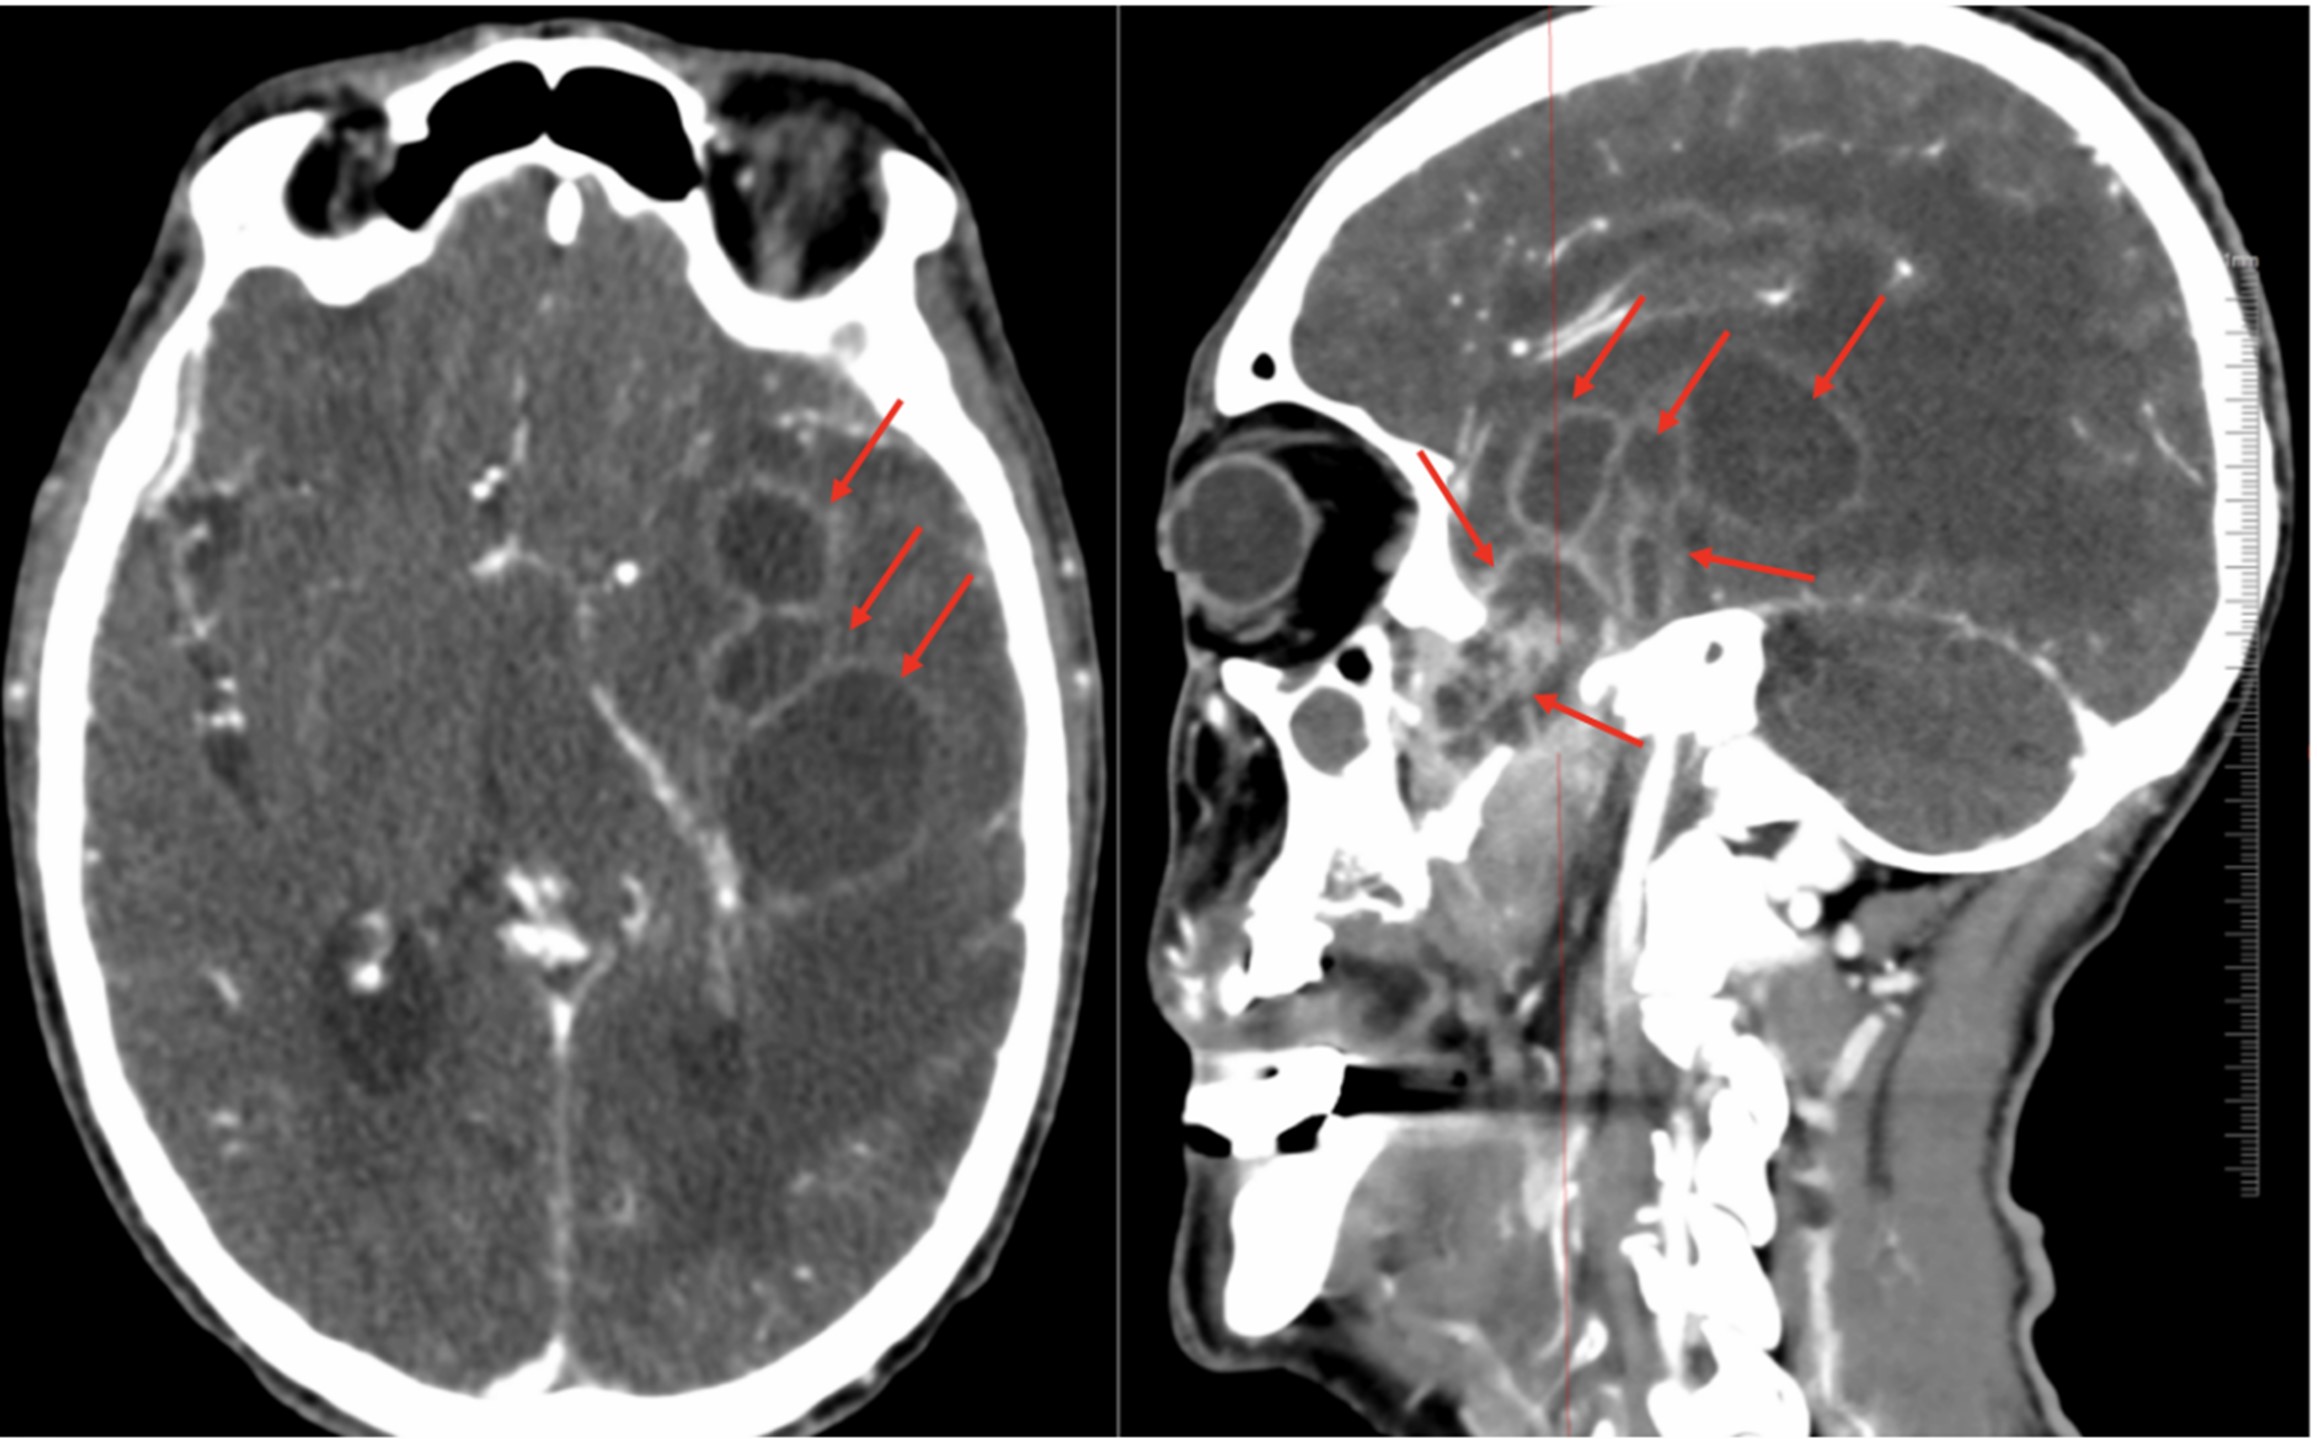

A 76-year-old man developed left temporoparietal pain with intermittent fever in January 2025. One month later, his condition worsened, with fever up to 39 °C, slowed responsiveness, disorganized speech, drowsiness, and poor cooperation on examination. He had a history of colorectal cancer surgery in 2006 with good recovery and no chemotherapy or targeted therapy. Laboratory tests performed upon admission showed elevated white blood cell count (WBC, 12.18 × 109/L), neutrophil (NEU%, 85%), high-sensitivity C-reactive protein (hsCRP, 38.71 mg/L), procalcitonin (PCT, 0.107 μg/L), and interleukin-6 (IL-6, 80.36 ng/L), along with reduced lymphocyte percentage (LYM%, 8.9%) and hemoglobin (Hgb, 87 g/L). Cranial CT revealed abscesses in the left frontal, temporal, and parietal lobes and the lateral ventricles, with right-sided hydrocephalus; chronic inflammation was present in the bilateral maxillary sinuses, left ethmoid sinus, and sphenoid sinus (Figure 1). Based on the laboratory results (i.e., elevated levels of inflammatory markers) and the imaging findings (i.e., cerebral abscesses), empirical antibacterial therapy and dehydration for intracranial pressure reduction were initiated. On day 4 of admission, endoscopic surgery was performed to remove lesions in the left sphenoid sinus–pterygopalatine fossa–middle cranial base. A direct smear of sphenoid tissue revealed septate hyphae with 45° branching (Figure 2). The presence of A. fumigatus was confirmed via culture and VITEK MS identification (Figure 3A–C). Cerebral Aspergillus abscess was thus considered, and voriconazole was initiated at a loading dose of 300 mg administered intravenously every 12 h, followed by a maintenance dose of 200 mg administered intravenously every 12 h. On day 7, repeat surgery was performed to reduce multiple intracranial abscesses via external ventricular drainage. Smear and culture of temporal lobe abscess samples showed that A. fumigatus was present. Histopathological analysis of sphenoid sinus and temporal lobe abscess samples showed brain tissue necrosis with extensive acute and chronic inflammatory cell infiltration and granuloma formation, as well as fungal clusters (Figure 4). Periodic acid–Schiff (PAS) stain and Grocott's methenamine silver (GMS) staining returned positive results. After treatment, the patient's mental status, headaches, and fever improved, and his muscle strength and tone in all four limbs were normal. On day 15, the laboratory test results showed a marked reduction in inflammatory markers. However, the patient was lost to follow-up after discharge (on day 25).

Figure 1. Cranial CT images showing cerebral abscesses in the left fronto-temporo-parietal lobe and lateral ventricle, hydrocephalus in the right hemisphere (red arrows), and chronic inflammation of the bilateral maxillary sinuses, left ethmoid sinus, and sphenoid sinus. CT, computerized tomography.